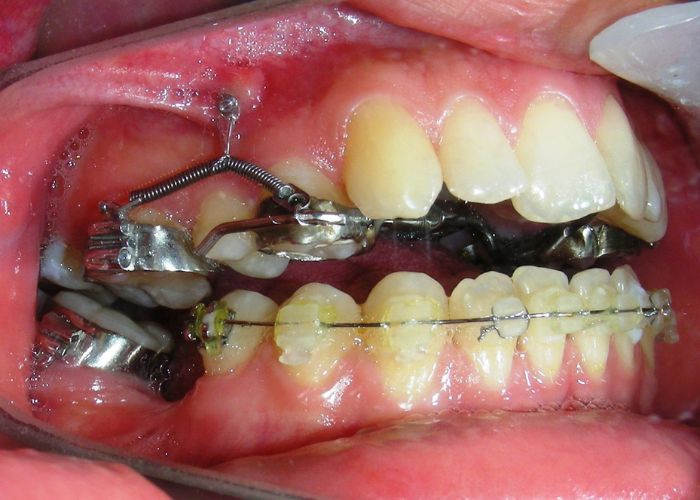

Was installed a Hyrax-type 10mm palatal expander of the Brazilian trademark Morelli® , modified by the author to be adapted to receive TADs microscrews, in order to initiate maxillary disjunction with MARPE (Mini-implant Assisted Rapid Palatal Expansion), TADS was installed with skeletal anchorage placed bilaterally having as references the roots of the maxillary canines and first premolars. Prior to insertion, local infiltrative anesthesia was administered using 2% lidocaine hydrochloride with 1:100,000 epinephrine. A total dose of approximately 0,8 mL per side (cortical infiltration technique). The TADs were inserted under aseptic conditions using a manual driver. Microscrew Evolution 1,6 Ø x 10 mm from the Argentine brand Odontit® . The Hyrax expander was then fitted and activated after 48 hrs .

Protocol of one activation per day was followed for a period of three weeks where the first clinical and radiographic evaluation was performed, showing clear signs of skeletal expansion, including the presence of a midline diastema. One more week of activations was added with a total of 28. The patient reported moderate headache during the first week of activation.

Having successfully achieved the expansion, we proceed to the intrusion of the posterior superior sectors, modifying the Hyrax by adding anchoring hooks at the buccal level of the first premolars. Using the Hyrax as anchorage, we sought a parallel intrusion. This could be replaced by a palatal bar. TADs were installed bilaterally at the mesial level of the first molars, inserting them as parallel as possible to the roots.

Simultaneously we begin with the alignment of the lower arch ,Simultaneously we began with the alignment of the lower arch with Roth prescription ceramic braces .022 . Henry Schein®

As the reader may infer, alignment and leveling of the upper anterior segment are being intentionally deferred at this stage of treatment. This strategic decision is based on the primary objective of closing the anterior open bite not through anterior extrusion, but by means of controlled posterior intrusion. This biomechanical approach promotes a counterclockwise rotation of the mandible, which leads to a increase in the facial axis angle and improvement in vertical facial proportions. By avoiding early anterior alignment, we prevent any premature vertical displacement of the upper incisors.